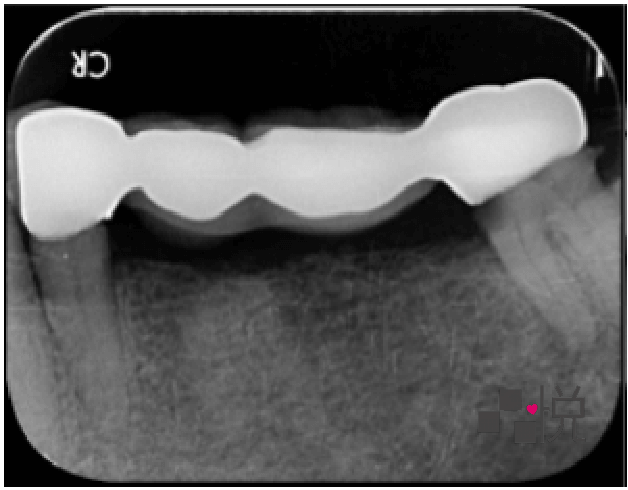

八年前將活動假牙換成植牙,一開始覺得很好用,開始大啖美食,但近年來常覺得臉頰關節不舒服。

八年前植牙採用一樣的咬合,一開始也沒有問題,但植牙後,享用更多美食,再加上年紀增長,關節開始出現退化現象,日漸出現疼痛。

過低的咬合也讓微笑曲線不好看,臉型變得較扁,嘴角塌陷顯得嚴肅。這些都可以透過改變全口的咬合來做改善。

饒醫師先使用咬合板提高咬合高度,王老師配戴後感到關節舒適許多,甚至不敢一日不戴咬合板入睡。

之後依照咬合版的高度製作臨時假牙,試戴兩個月後,確認發音、咀嚼、外觀都沒有問題,便更換為正式假牙完成治療。